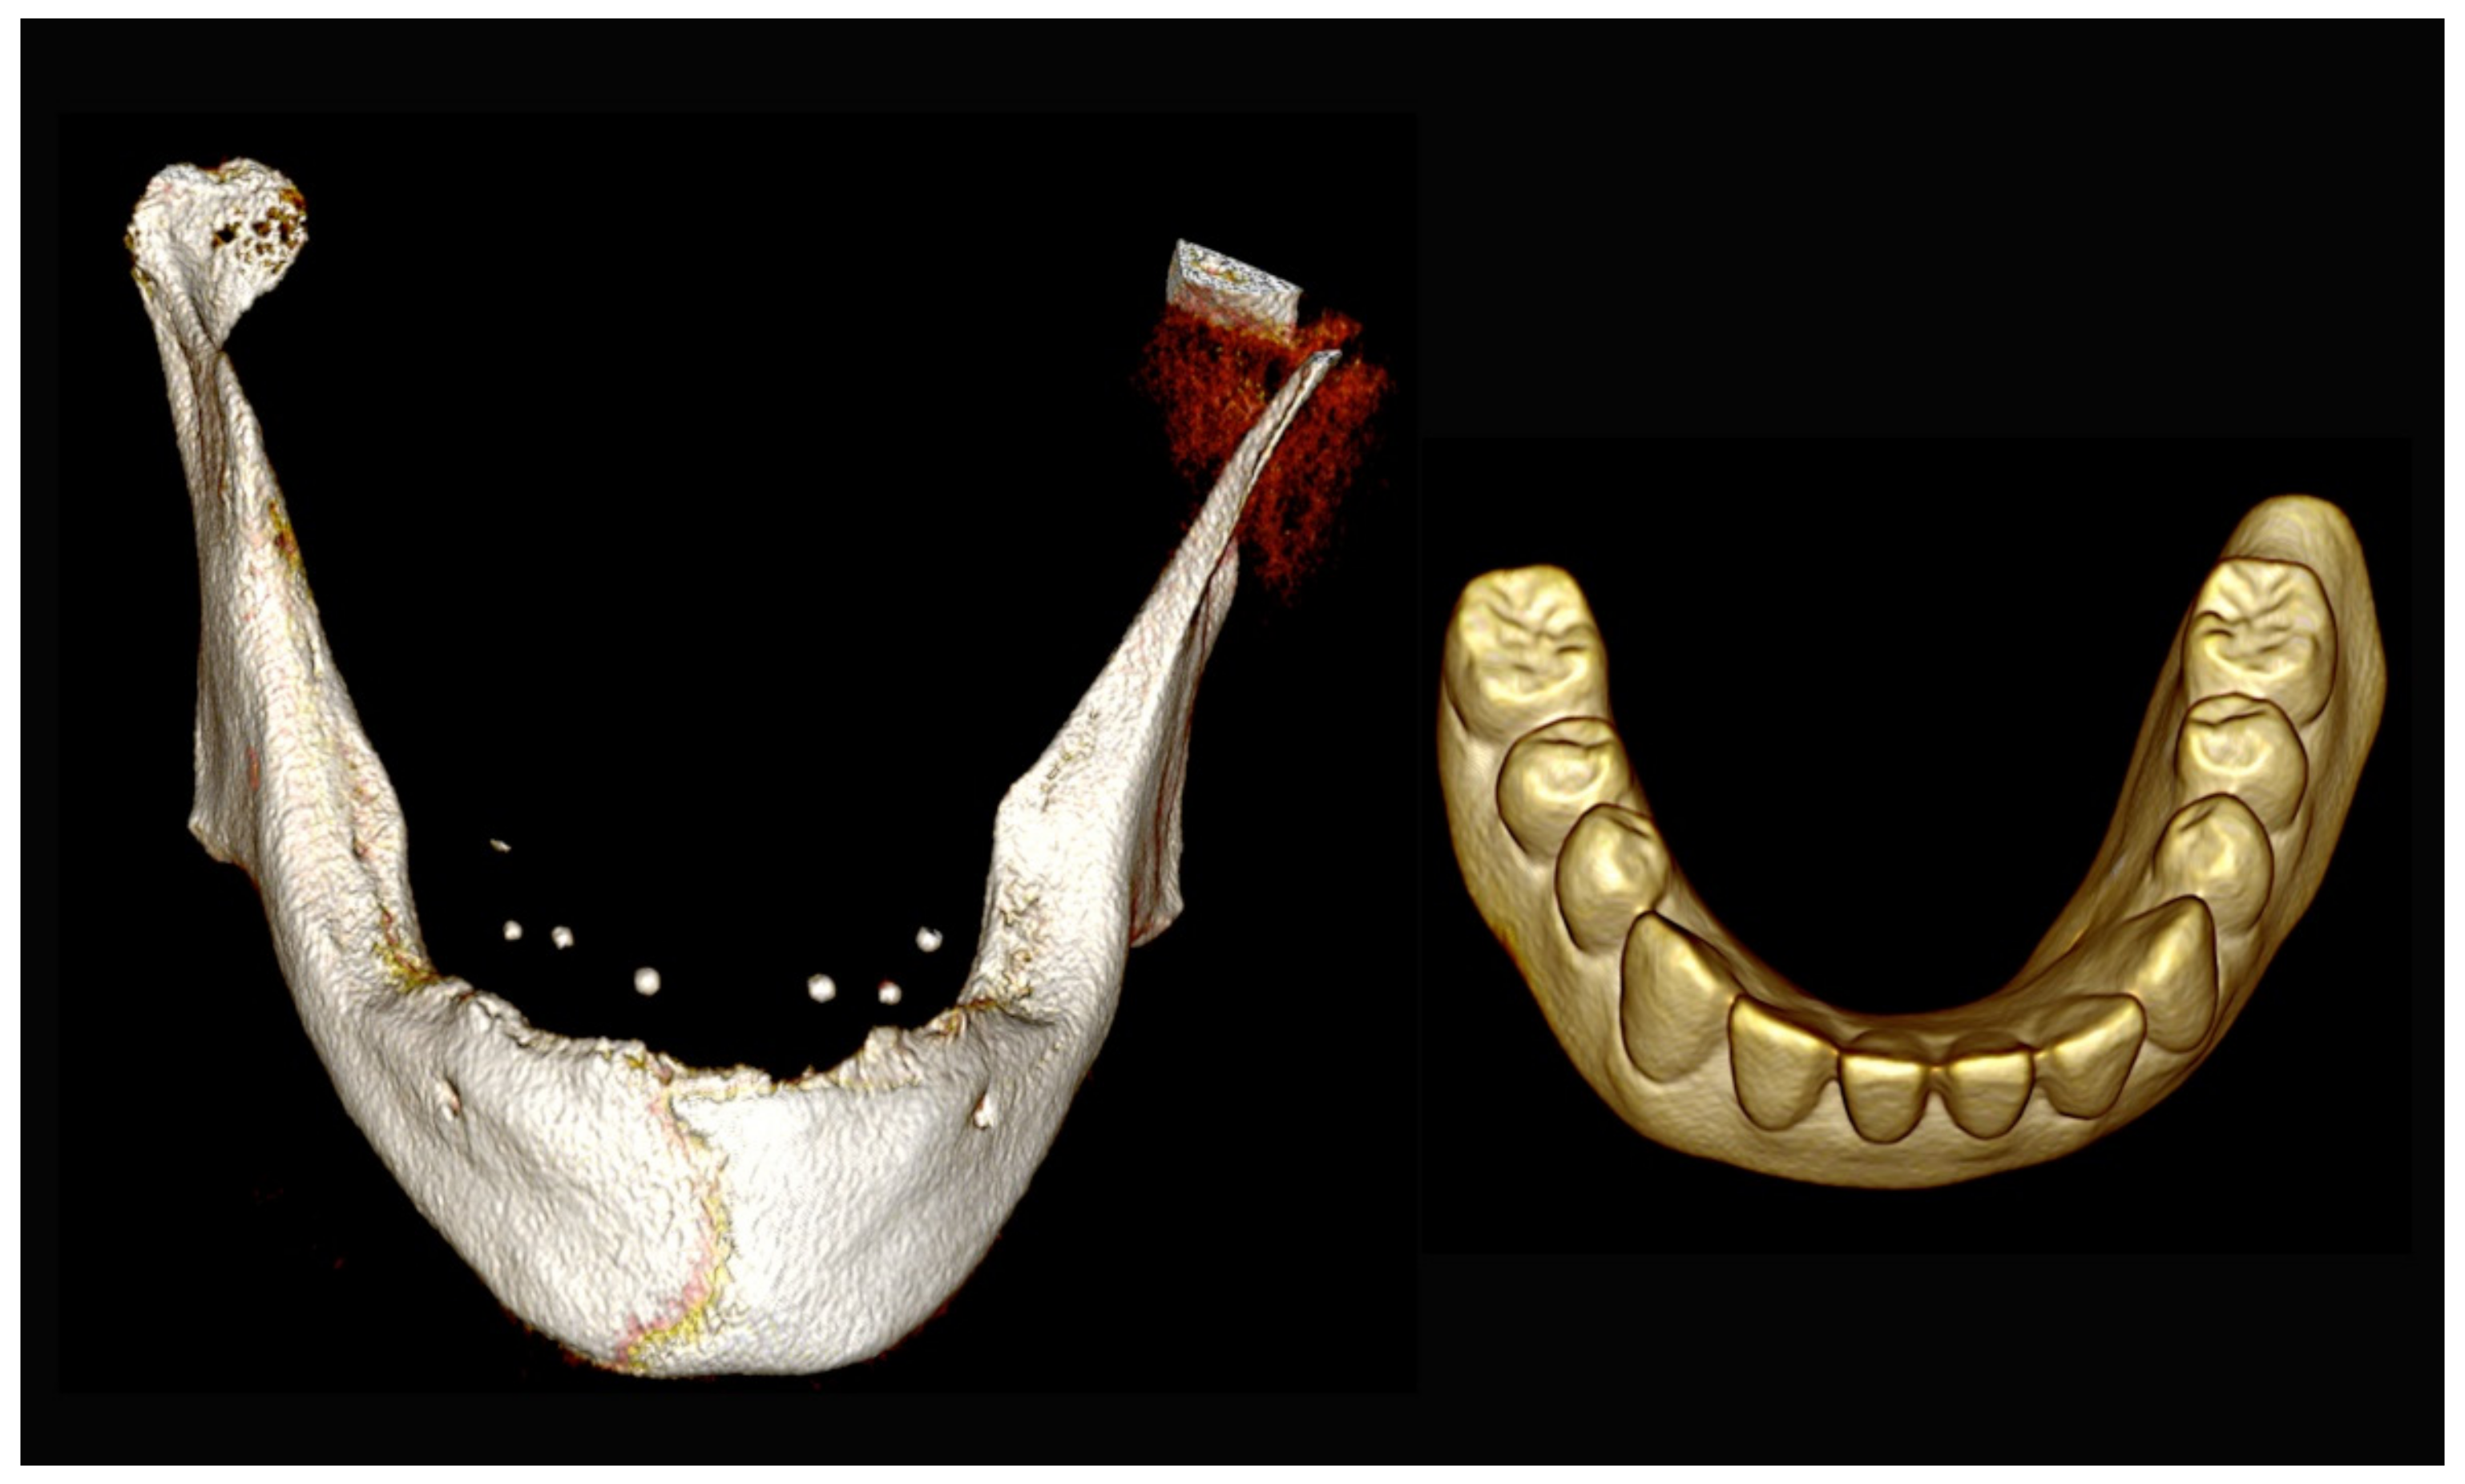

6.3.3. Image Segmentation and Virtual Planning:

6.3.4. Intra-Operative Documentation: